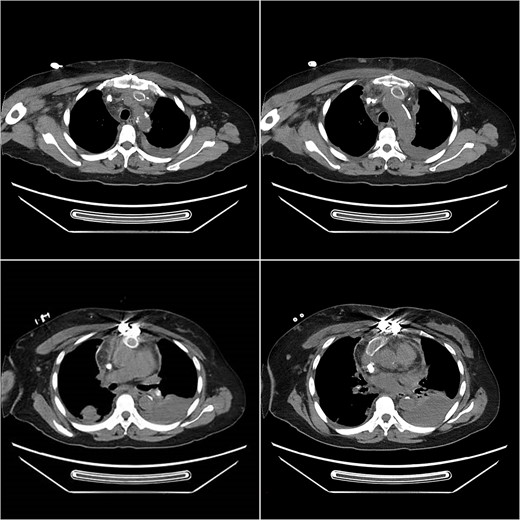

Postoperative computed tomography angiography (CTA) showed no contrast agent leakage in the artificial blood vessel.

Postoperative computed tomography (CT) three-dimensional reconstruction shows the artificial blood vessel and tunneled cuffed catheter deformation.